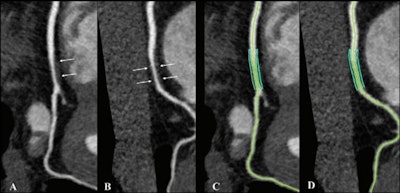

Noncalcified coronary plaque in an asymptomatic 52-year-old man living with HIV with a 10-year Framingham risk of 5%. Images show 256-section contrast-enhanced coronary CT angiography with electrocardiographic gating and curve reformat. (A, B) CT scan shows a smooth noncalcified plaque in the right coronary artery (arrows) with 70%-80% stenosis. (C, D) The right coronary artery plaque volume was 130 mm3 (green lines).In part due to antiretroviral therapy, people with HIV are living longer and thus may experience age-related conditions such as coronary artery disease, the group wrote. Studies have suggested that they have a greater risk of heart attack than people who aren't infected, but the reasons for this are unclear. Inflammation and immune dysfunction could play a role.